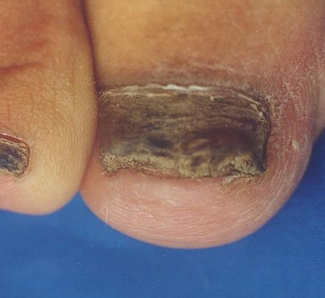

1、灰指甲分为两种类型。一种为白甲型,主是从甲根开始,在甲板表面会出现一些小白点,逐步扩大,造成甲板变软下陷指甲表面变得凸凹不平。另一种是从甲缘和侧壁开始,致使甲板凹陷,慢慢发展导致甲板松脆、指甲增厚、碎裂,以至变黑,指甲表面粗糙无光泽,还会变得一层一层的。

6、远端甲下型灰指甲的症状:病发前期表现为甲的远端甲板出现不规则的小白斑,之后逐渐变成没有光泽的灰色小斑,直至变为黑色或深棕色。很快甲板就会变质,甲下角的兼职开始碎屑堆积、甲床增厚。最后甲板萎缩并伴有出血状况。